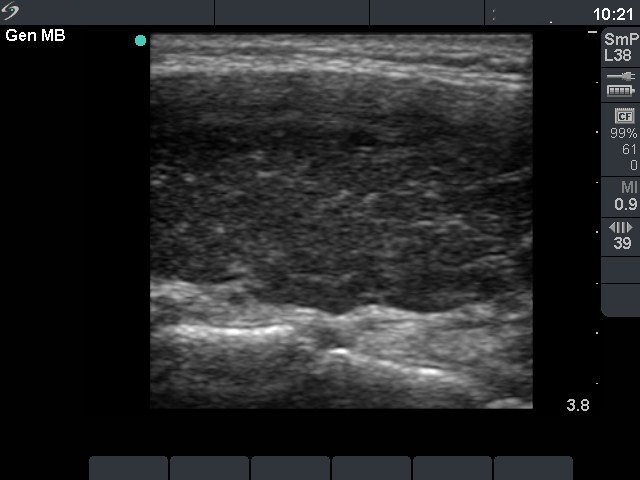

First investigation 6 months after delivery (first and second rows of images)

Clinical presentation: a 22-year-old woman was referred for an evaluation of a newly discovered hypothyroidism. She had fatigue and hair loss. She has been delivered 6 months before present investigation.

Palpation: the thyroids were enlarged and firm.

Functional state: hypothyroidism with TSH 47.7 mIU/L.

Ultrasonography: the thyroids were hypoechogenic without any nodule. The vascularization was increased.Cytology resulted in Hashimoto's thyroiditis.

Clinical diagnosis: hypothyroidism, post partum thyroiditis.